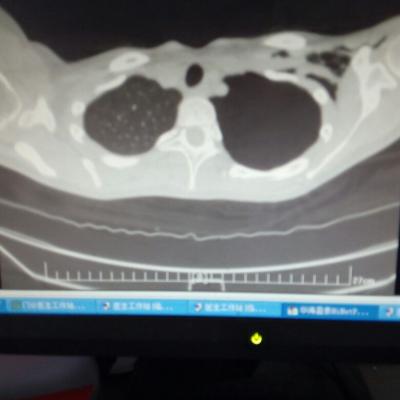

主诉:反酸、烧心5年,加重1年。 病史:患者5年前饮酒出现反酸烧心,并嗳气症状,剑突下烧灼感,饮酒及平卧后加重,无恶心呕吐,无腹痛腹泻,无吞咽困难,服用“达喜”后症状可缓解,易反复发作。3天前我科门诊示:胃镜反流性食管炎(LA-B),现为进一步诊治入院。

1.胃食管反流病 1.1反流性食管炎LA-B 2.食管裂孔疝 处理:患者诊断明确,行腹腔镜下食管裂孔疝修补术+胃底折叠术。

患者术后一周出院,反酸、烧心、嗳气症状明显缓解,无吞咽不畅等症状。 讨论:对于诊断有食管裂孔疝病人的胃食管反流病,且用药有一定疗效,建议行手术治疗,行腹腔镜下食管裂孔疝修补术,修补了膈裂孔,同时行胃底折叠术,加紧了贲门括约肌压力,共同形成抗“反流瓣”。